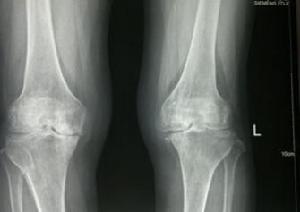

5.膝關節正、側位X照片,顯示髕骨、股骨髁、脛骨平台關節緣呈唇樣骨質增生,脛骨髁間隆突變尖,關節間隙變窄,軟骨下骨質緻密,有時可見關節內游離體。